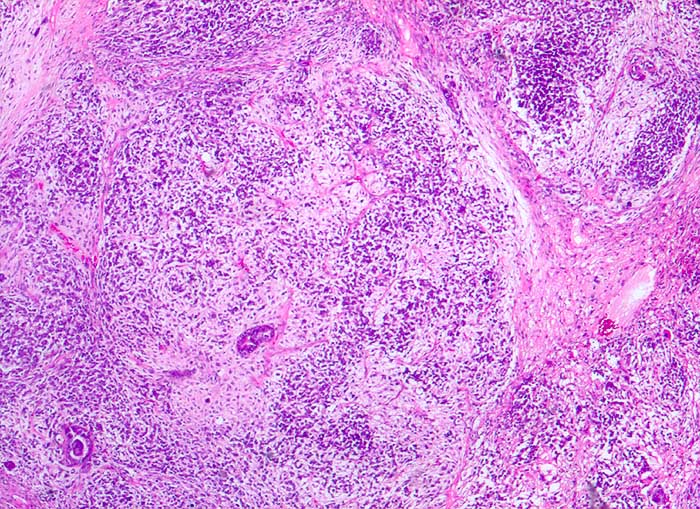

Müllersche Mischtumoren bestehen aus einer epithelialen und einer mesenchymalen Komponente. Die epitheliale Komponente ist in der Regel ein Adenokarzinom. Die Sarkomkomponente kann homolog (Leiomyosarkom, Stromasarkom, Fibrosarkom) oder heterolog (Rhabdomyosarkom, Chondrosarkom...) sein also nicht aus ortsständigem Mesenchym entstammend. Am häufigsten treten diese Tumoren im Uteruscavum auf. Sie können aber auch in anderen Lokalisationen des Genitaltrakts vorkommen. Die Ausstriche enthalten ein buntes Zellbild mit deutlich atypischen Zellen. Wenn neben Karzinomzellen auch atypische mesenchymale Zellen vorhanden sind, kann zytologisch die Diagnose eines malignen Müllerschen Mischtumors gestellt werden.